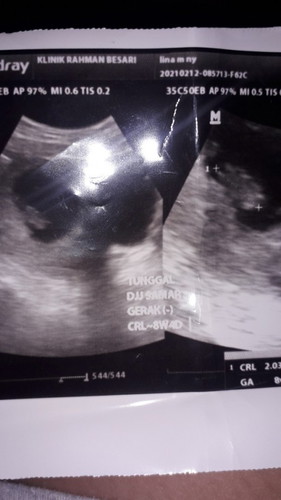

Sore bunda bun saya mau tanya apakah normal jika hamil 8minggu 4hari detak jantung masih samar dan belum ada pergerakan ..saya kmarin lupa nanya kedokternya karna saking senang nya liat calon janin..apakh disini ada yg sama bunda keluhan nya..#seriusnanya #bantusharing #ingintahu #jangandibully #firstbaby #mommybuntu